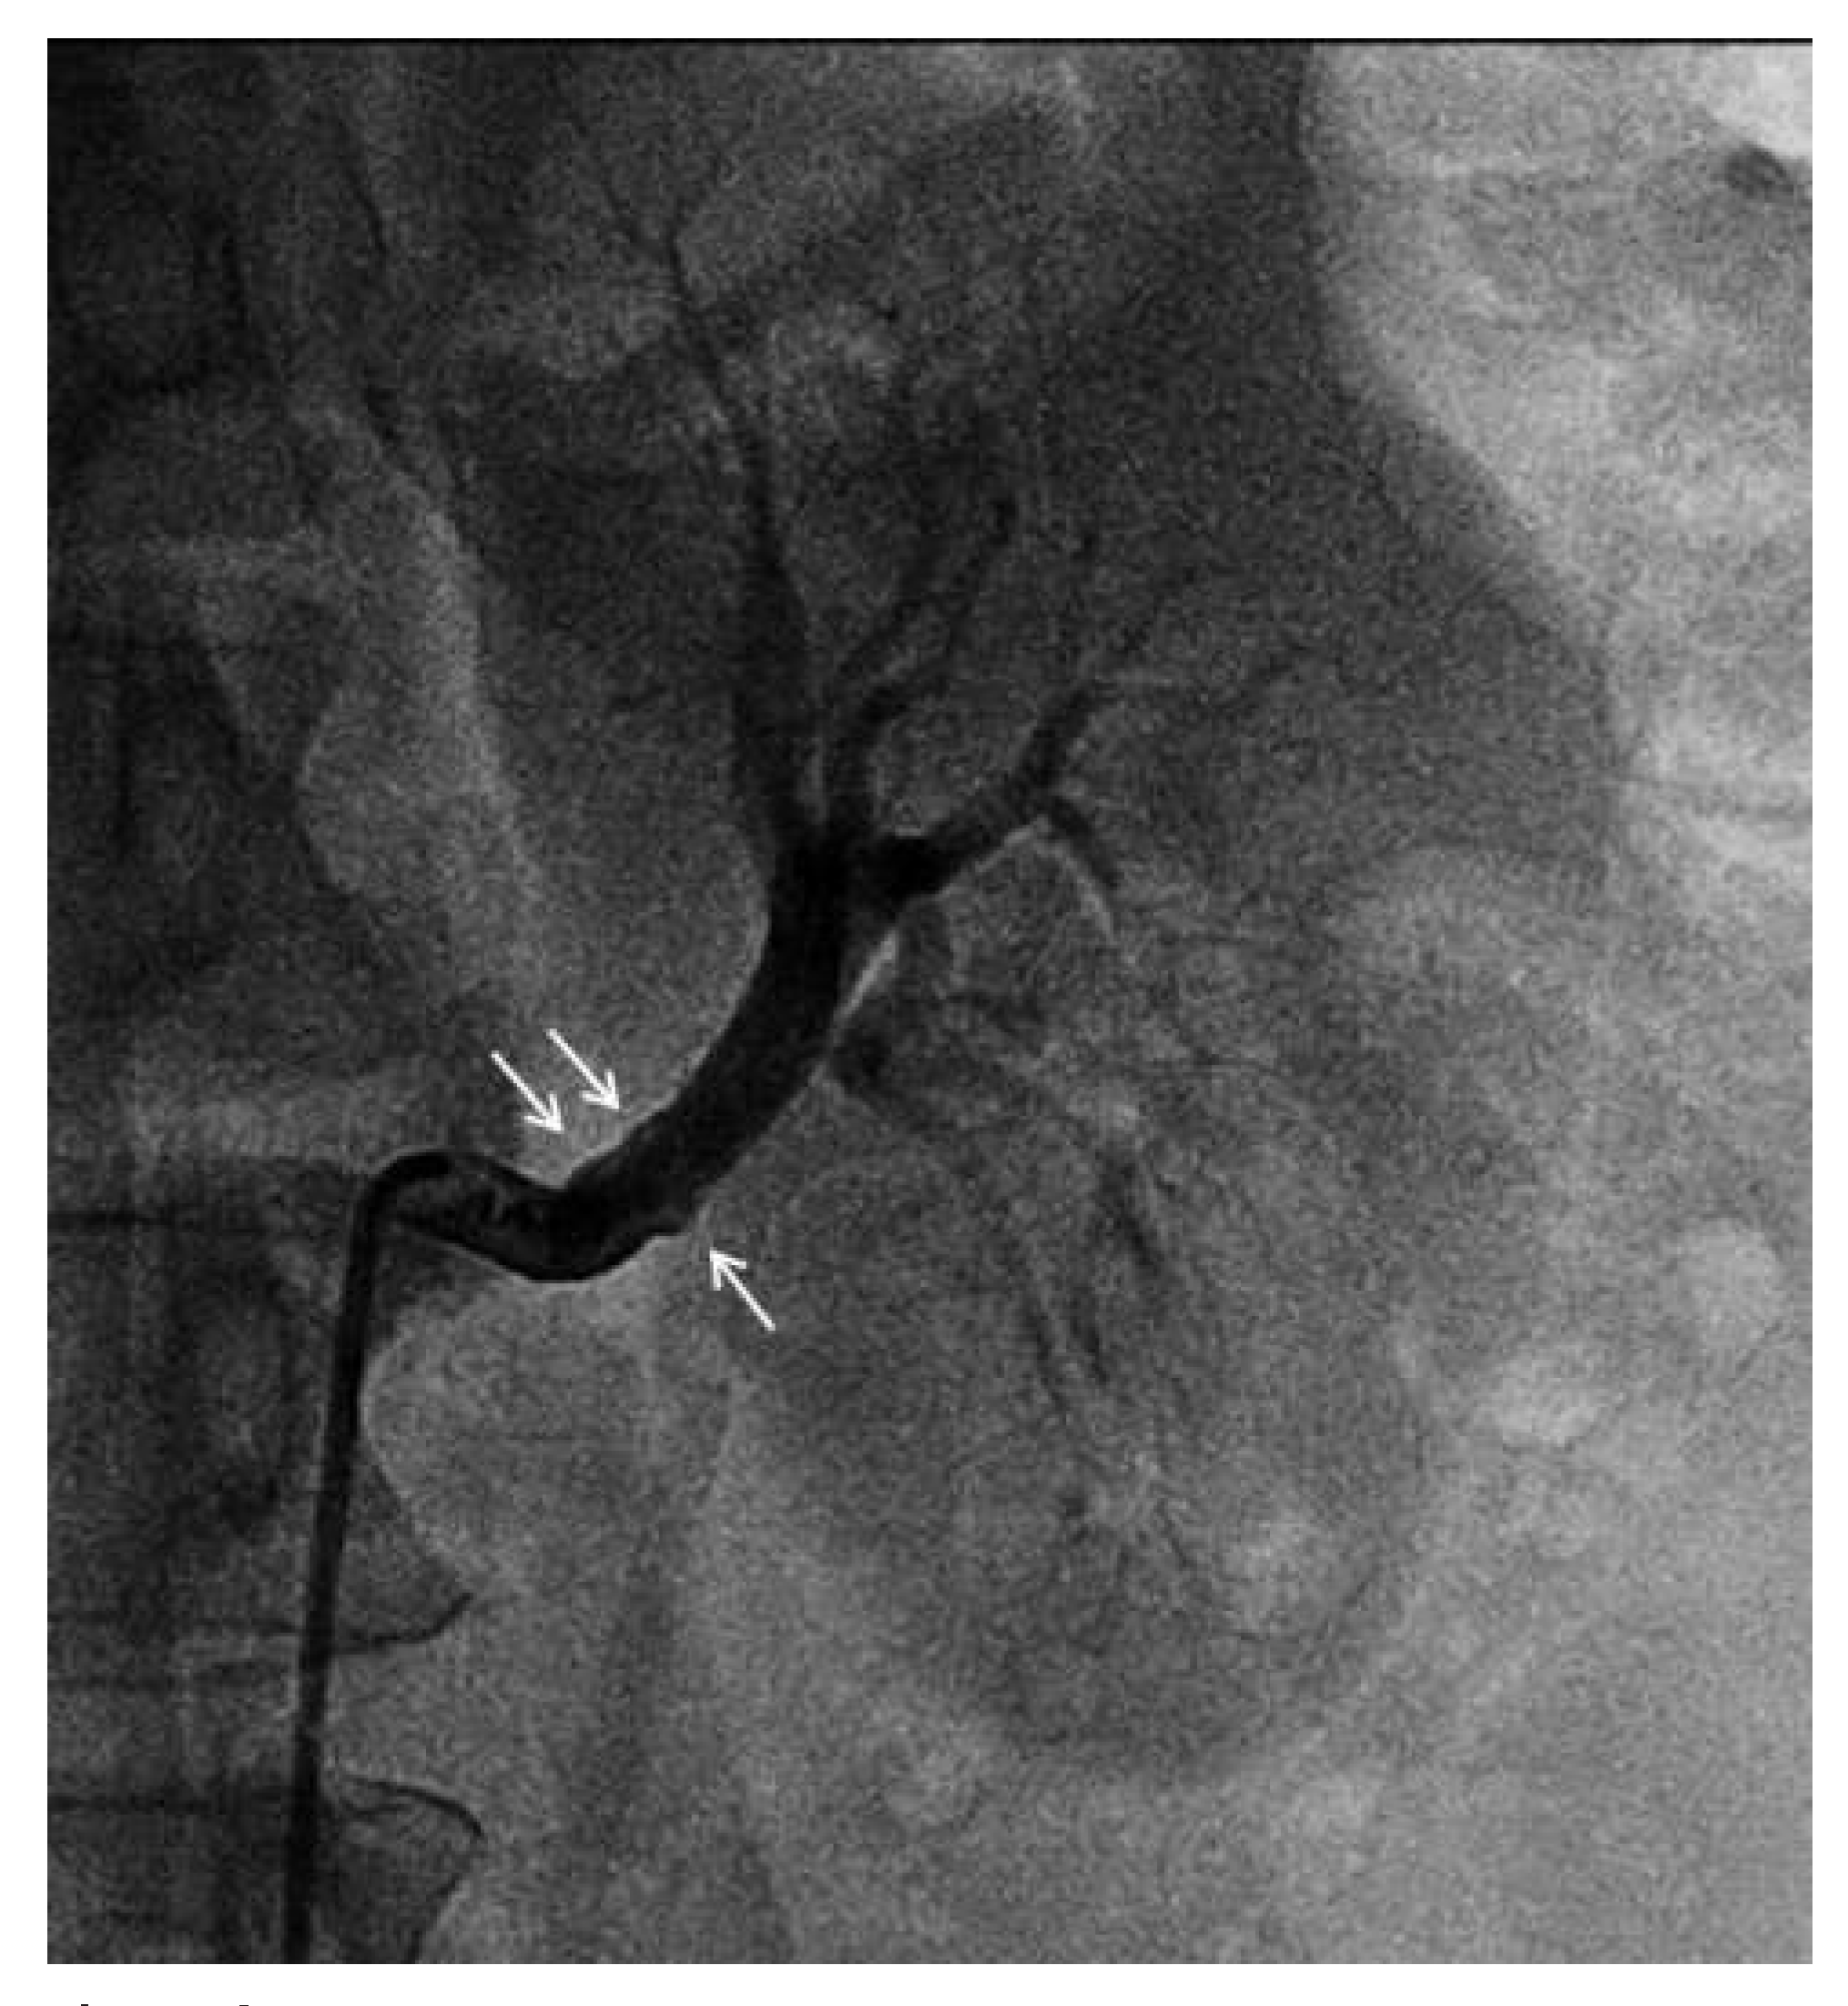

Case Description

Coronary FMD

Spontaneous coronary artery dissection as the complication of coronary FMD

Diagnosis